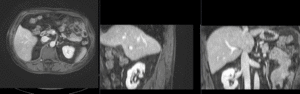

affine registered MRI & CT

nonrigid registered MRI & CT